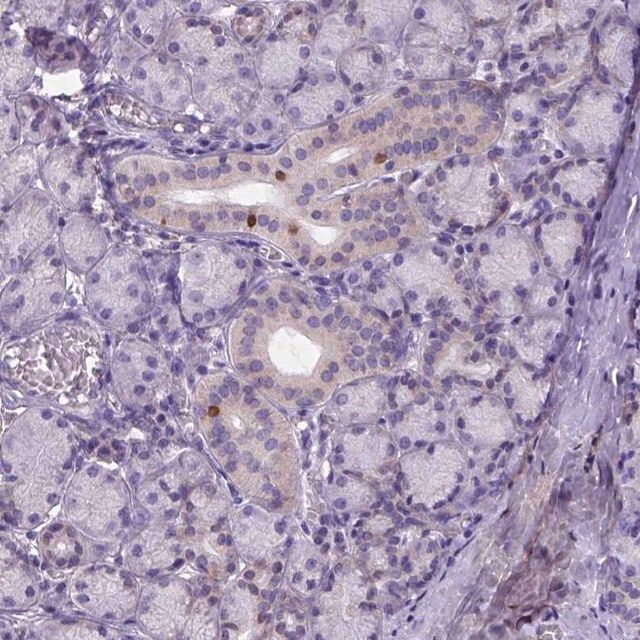

Forkhead box protein I1a (FOXI1), also known as HNF-3/fork-head homolog 3, is a transcriptional activator with a DNA binding motif and belongs to forkhead-box (FOX) family. The FOXI1 is mapped to human chromosome 5q35.1.

Anti-FOXI1 antibody produced in rabbit has been used for the detection of FOXI1 in human bronchial epithelial cells using immunofluorescence technique.

Forkhead box protein I1a (FOXI1) regulates the function of vacuolar ATPases in endolymphatic epithelium in ear, epididymis and kidney. The interaction of FoxI1 with microRNA, miR-491-5p, wingless/integrated (wnt) and β-catenin plays an important role in the progression of gastric cancer.

- IHC tissue array of 44 normal human tissues and 20 of the most common cancer type tissues.